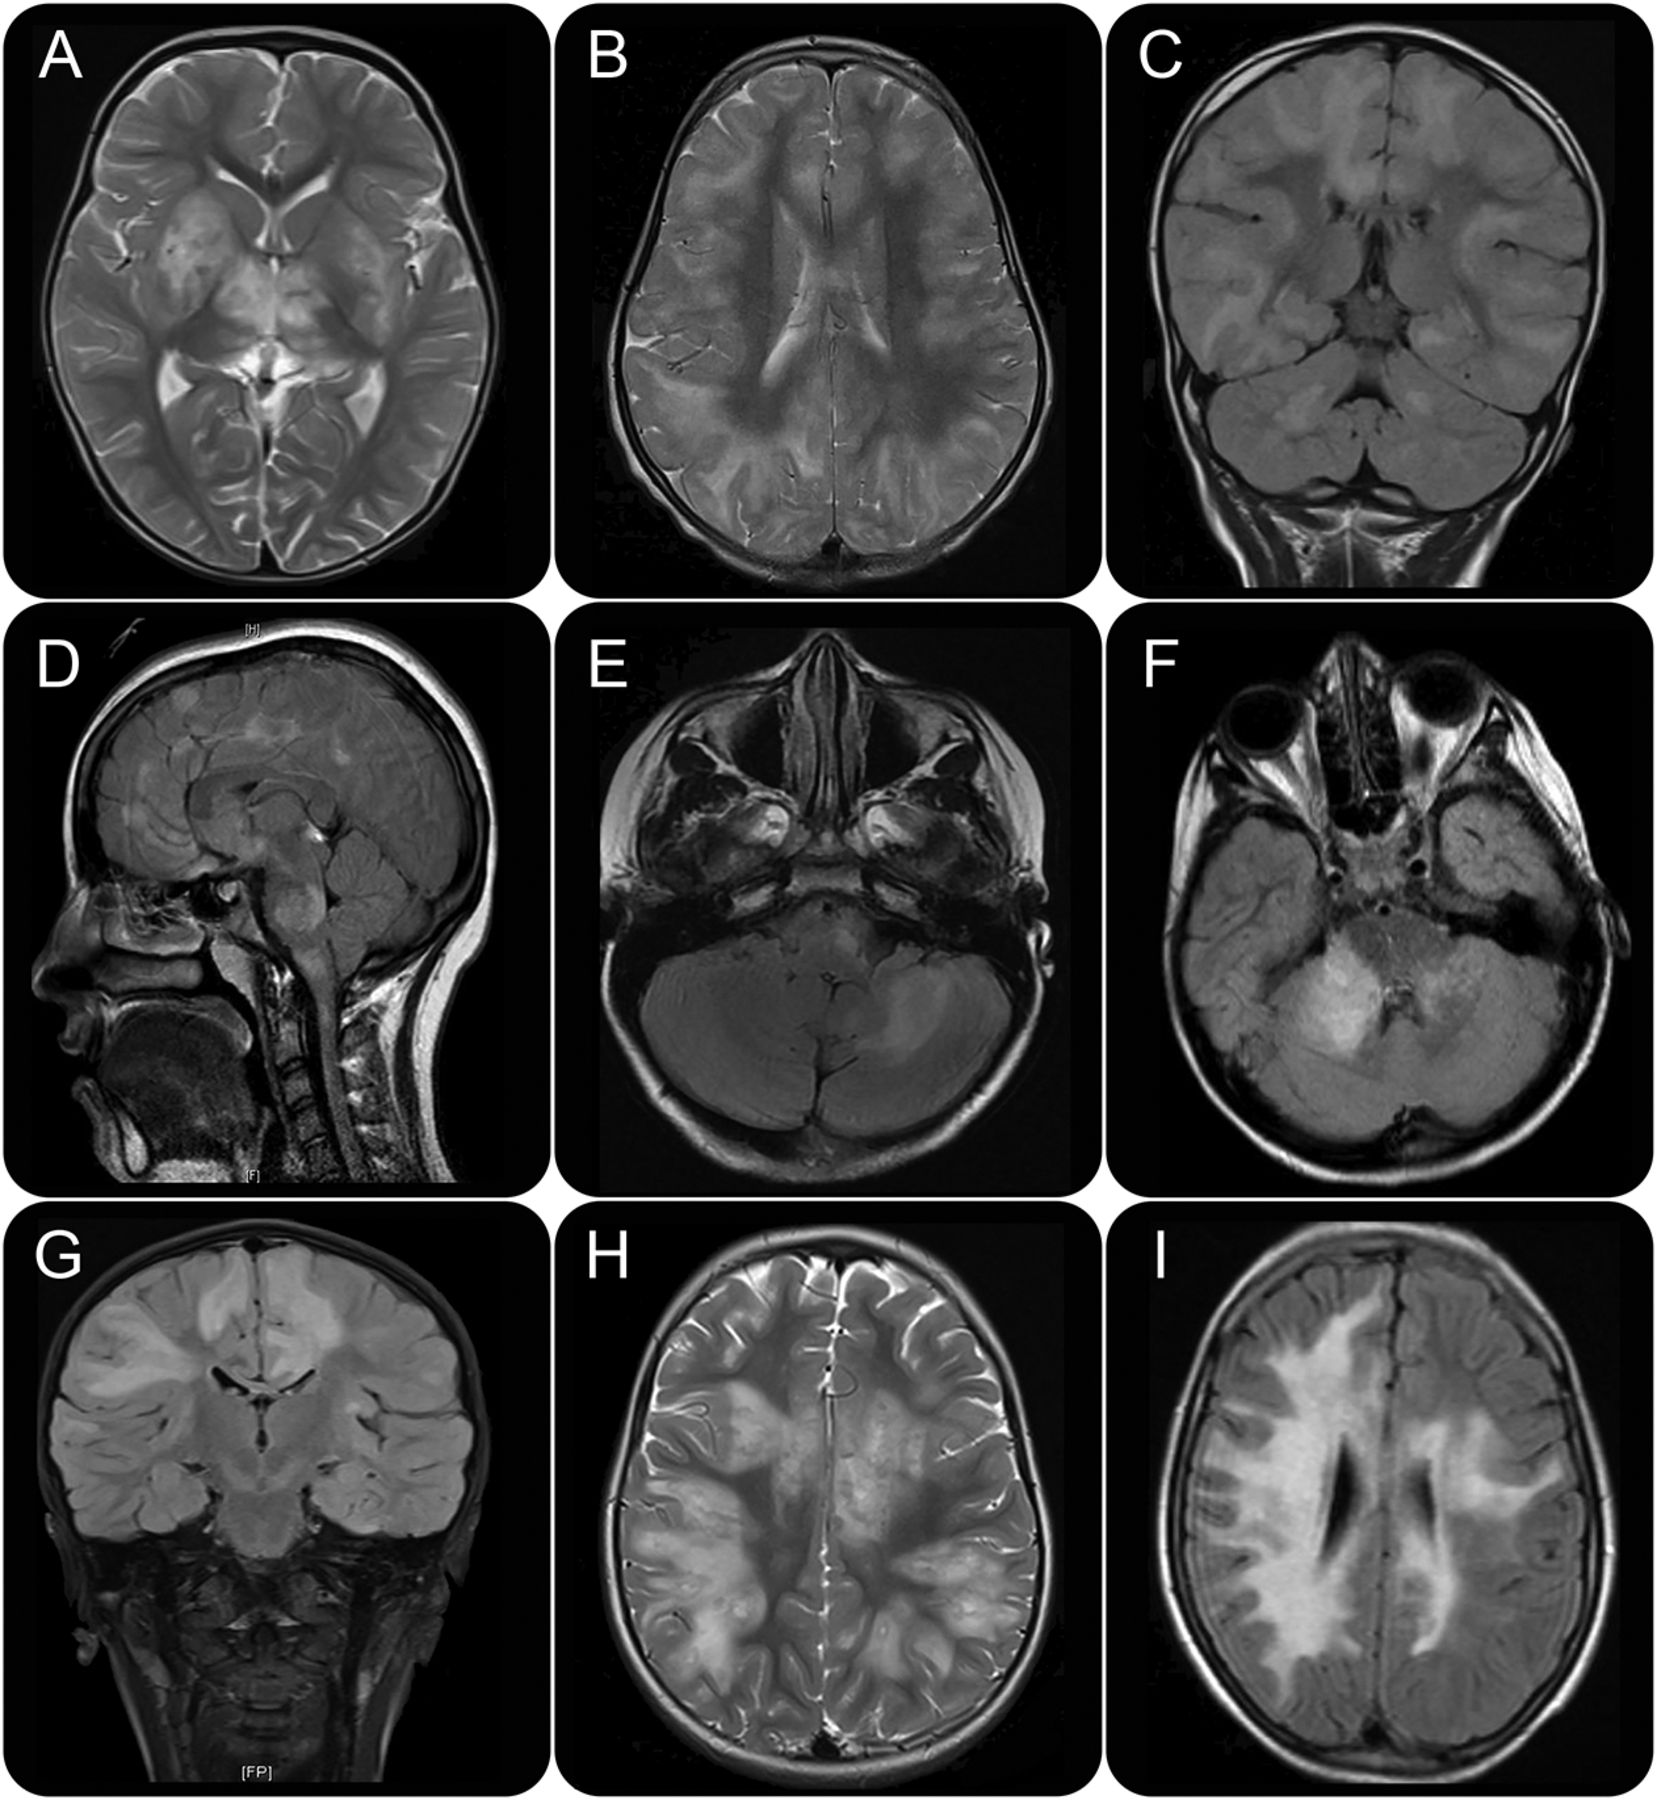

蒙蔽放射分析。

三分之一neuroradiologist (F.B.)执行一个单独的分析来评估是否单独成像特点可以支持一个特定综合征的诊断而盲的临床特征和Ab的结果。下面分别分析重复基线MRI和后续的扫描。病变形态、分布和位置是用于支持面向诊断斑块是椭圆形女士和女士的垂直于心室表面。他们发生双边的,但通常是不对称的,他们分布在幕上的和infratentorial隔间。虽然病变女士可以坐落在中枢神经系统的任何地方,他们经常看到juxtacortical,室旁,infratentorial地区。19核磁共振扫描被分成以下类别;(1)不是女士,(2)不典型的女士,(3)一些女士的特性,或(4)典型的女士。

类别1和2,以下5个主要成像模式之一,其中包括功能与NMOSD有关6,20.最近报道MOG-Ab患者和特性,13,21neuroradiologist被选为主要模式:(1)疾病局部脑干和下丘脑;(2)主要支流,朦胧的/不加边涉及灰质和白质病变;(3)广泛的支流leukodystrophy-like MRI模式;(4)大幅划定半球白质病变(> 3厘米);或(5)TM和/或颅内外观正常或非特异性的白质病变。此外,对于后续的扫描,2后成像特性寻找:几乎或完全解决损伤和破坏性病变,定义为严重的组织导致中央低信号稀疏fluid-attenuated反转恢复与体积相关的损失。

最后,中脑病变的存在,背侧脑干,periependymal侧脑室周围,纵向广泛TM (LETM),大脑皮层灰质,丘脑、基底神经节,juxtacortical和深白色板牙参与多室,小脑总花梗,脑桥和视神经/大片,被认为是典型的患者与AQP4-Ab NMOSD——(根据Wingerchuk et al6标准)20.和MOG-Ab-associated髓鞘脱失,被记录。

基线的盲法分析MRI扫描,在所有110名患者,正确确定58 62 (93.6%;52在4级,6在3级)女士的孩子和所有48个孩子非MS (100%;38在类别1;10在类别2)。随访MRI扫描分析女士确认只有一个额外的2例(4 MS患者的MRI扫描非典型成像如图飞行)。脊髓损伤患者45所短段脊髓炎,与12的13个病人在非ms组LETM (p< 0.0001)。

当核磁共振成像模式和病变位置之间MOG-Ab AQP4-Ab-positive患者相比,AQP4-Ab患者更有可能有疾病仅限于脑干和下丘脑(发病:38% vs 0%,p= 0.0094;在随访:50% vs 0%,p= 0.0015)。破坏性病变在随访扫描被认为在大多数AQP4-Ab-positive患者(62.5%)和没有MOG-positive患者(p= 0.002)(表3和图)的军医。病变位于背侧脑干AQP4-Ab-positive患者更常见(87.5% vs 11.5%,p= 0.0085),而在小脑病变总花梗被认为只有MOG-positive患者在发病和随访(p= 0.03,p= 0.011)(表3和图1)。最后,leukodystrophy-like病变被认为只有在MOG-Ab-positive患者(表3和图1)。

蒙蔽了核磁共振分析成功区分女士和非MS案件已经开始。MRI异常AQP4-Ab-positive脑干和下丘脑是典型的病人,如前所报道,38而不明确的病变在小脑脚被认为只MOG-Ab-positive病人。未来的研究将致力于确认这是否可以用作MOG-Ab-associated疾病的标志。